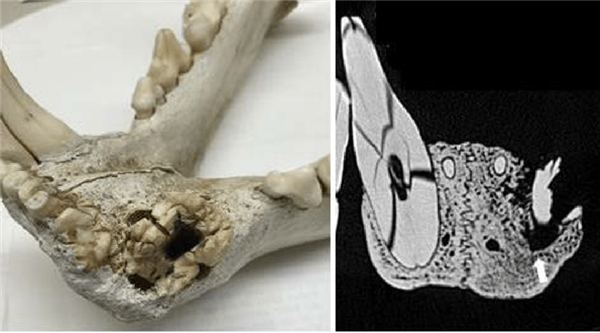

研究團(tuán)隊(duì)還檢查了遺留下來(lái)的獅子骸骨,竟然在2具獅子骸骨中發(fā)現(xiàn)了深入骨頭的豪豬刺傷口。

1965年,肯尼亞地區(qū)出現(xiàn)了一頭讓人聞風(fēng)喪膽的食人獅,綽號(hào)“達(dá)拉賈尼食人獸”,據(jù)說(shuō)這頭怪獸殺死了至少50人,將其獵殺后,人們?cè)谒谋亲幽抢锇l(fā)現(xiàn)了一根豪豬刺。

對(duì)骨頭進(jìn)行掃描,發(fā)現(xiàn)刺總長(zhǎng)度有23cm,扎入鼻子里的深度超過(guò)5cm。

還有一具保存在博物館的獅子遺骸,牙齒里也卡著一根3厘米長(zhǎng)的豪豬刺。